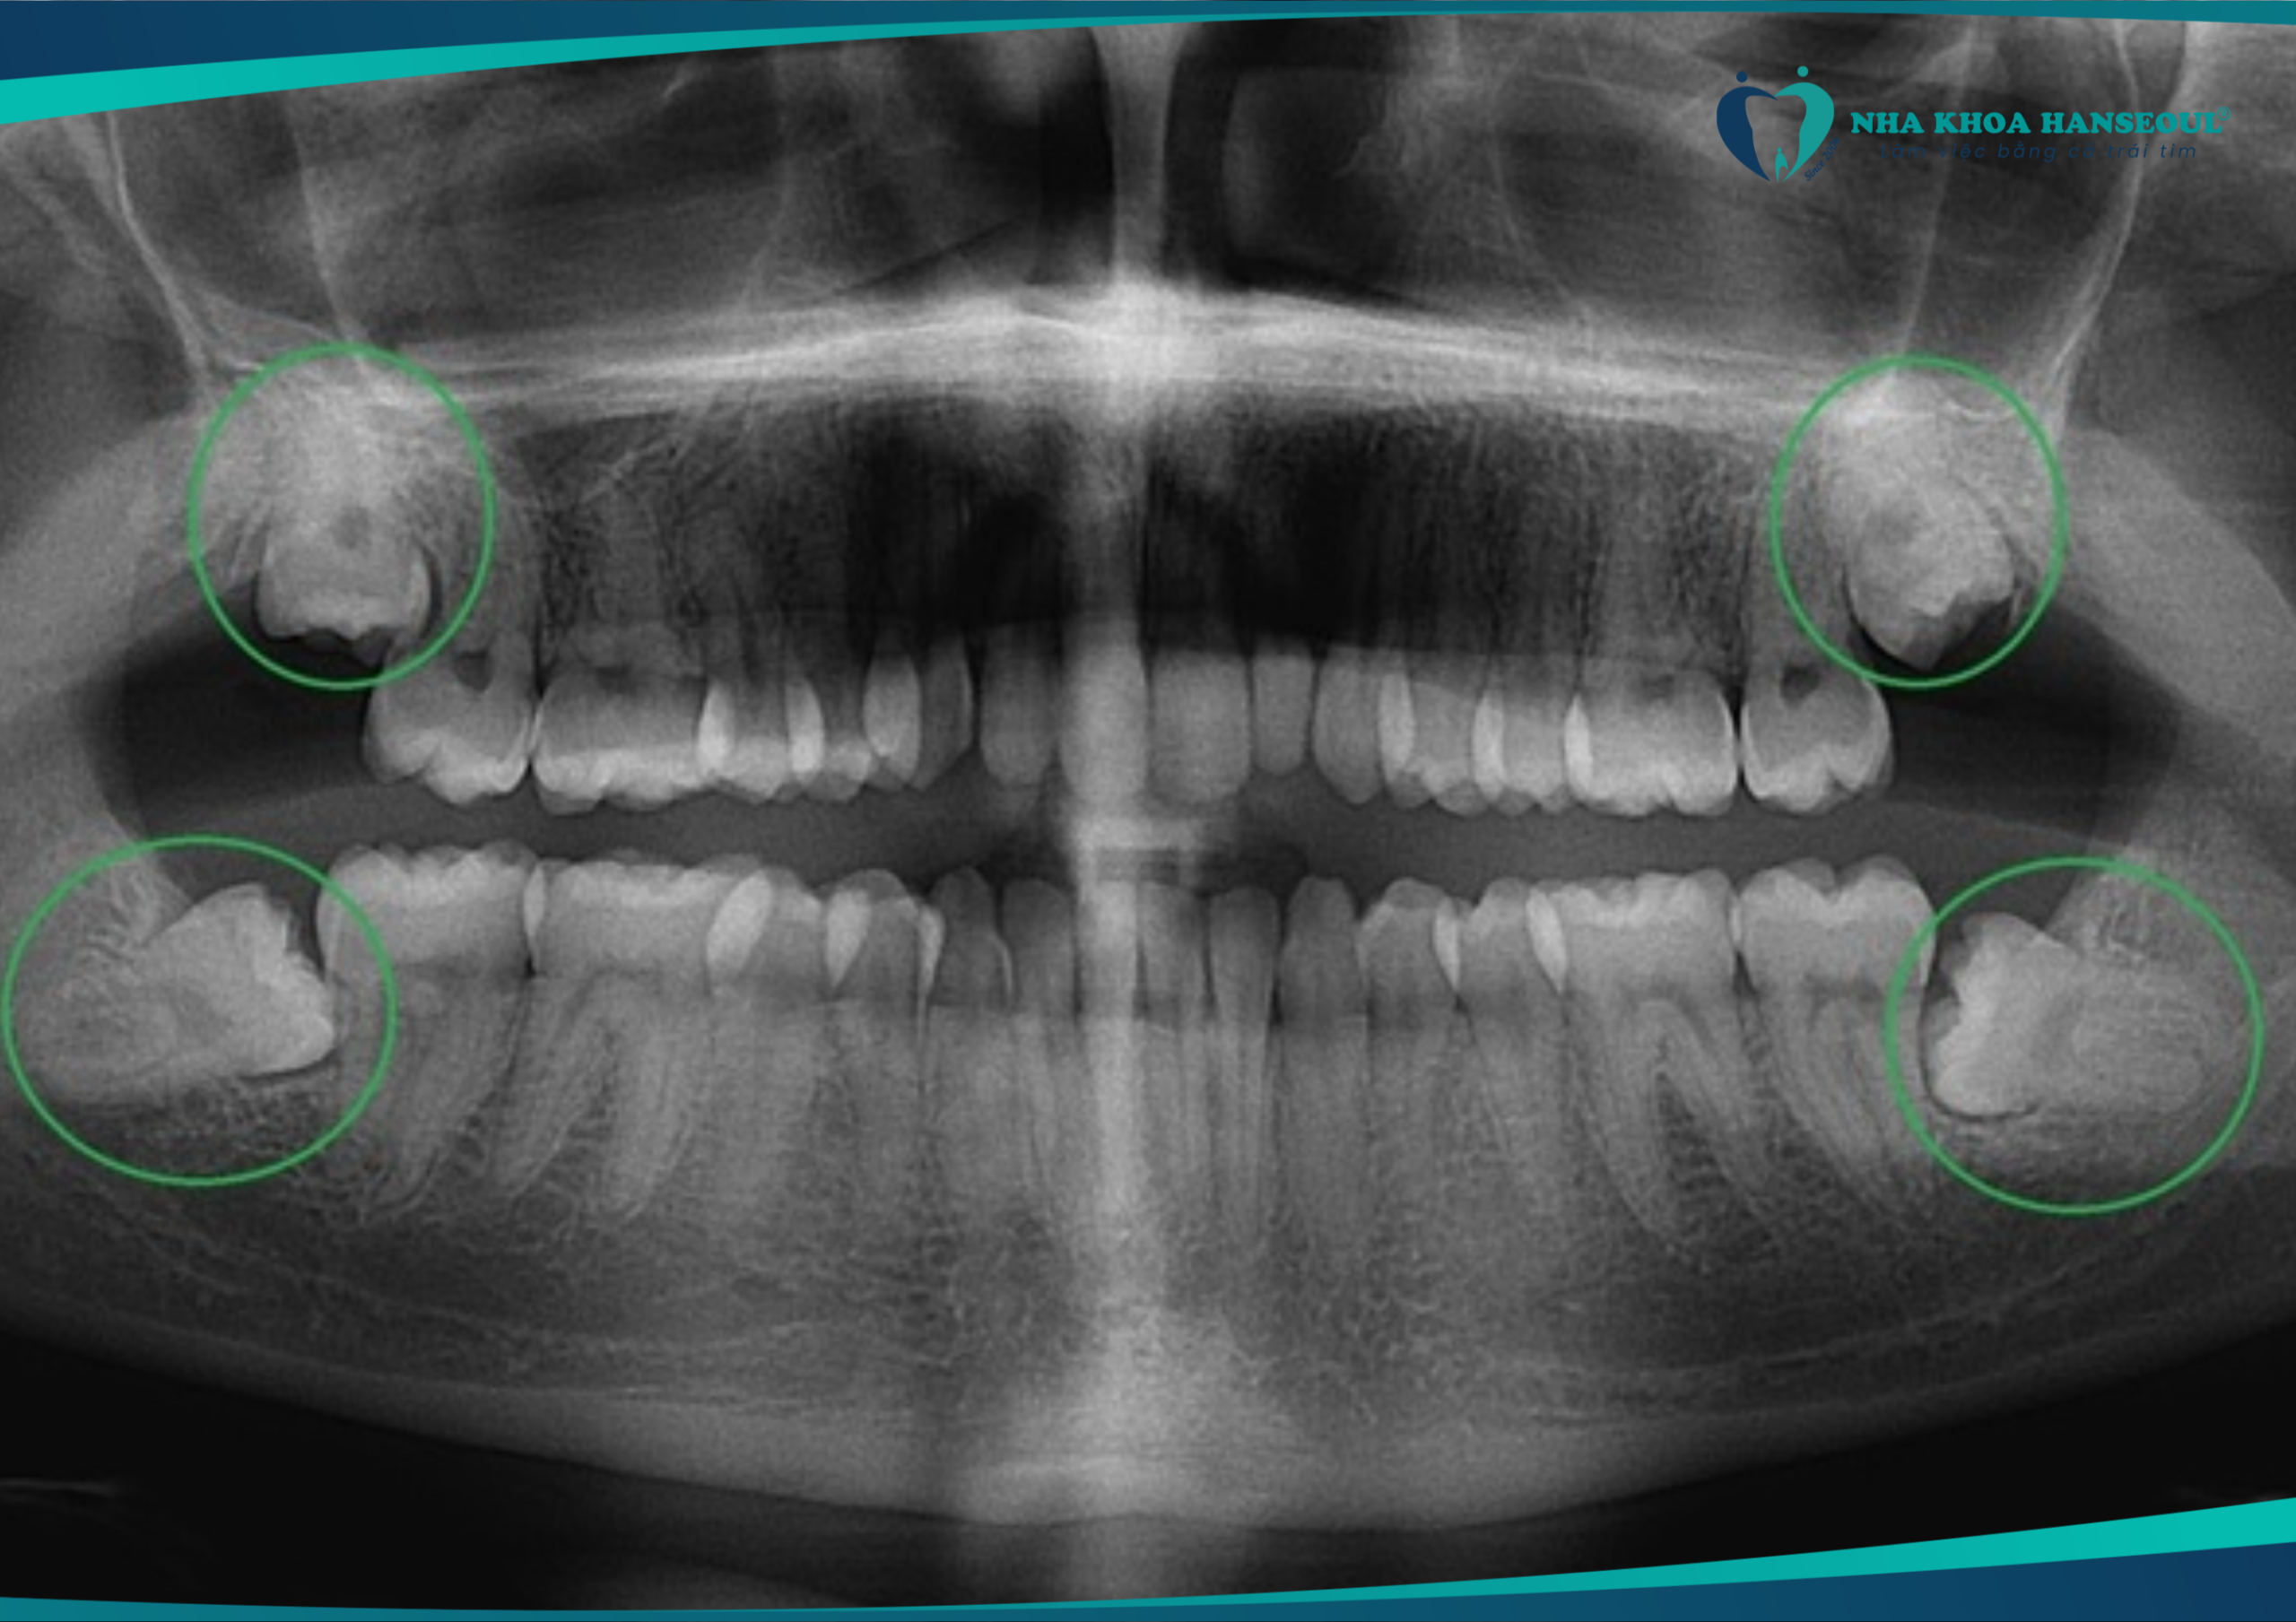

Răng số 8 không đau có nên nhổ không? Chuyên gia nói gì?